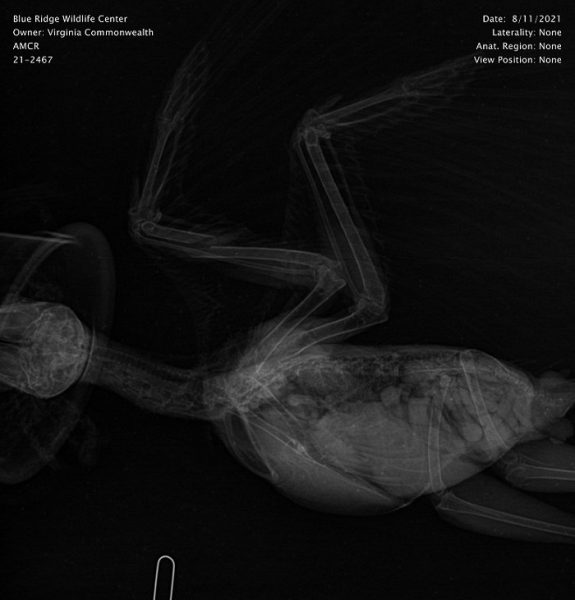

This radiograph shows the American Crow on the day of admission. The left ulna (the thicker bone on the wing that is closest to the head in this image) is fractured. Had the bone been well-aligned, a simple bandage would have been sufficient to stabilize the fracture and allow for healing. In this case, we felt that there would be better healing with surgical stabilization. Wild animals must be able to get around well, find food, and live without chronic pain. The bone simply healing together is rarely good enough. It needs to be fully functional. To give this bird the best chance of long-term survival, surgery was performed.

After surgery, follow up radiographs are taken to ensure that the bone segments are positioned well for healing.